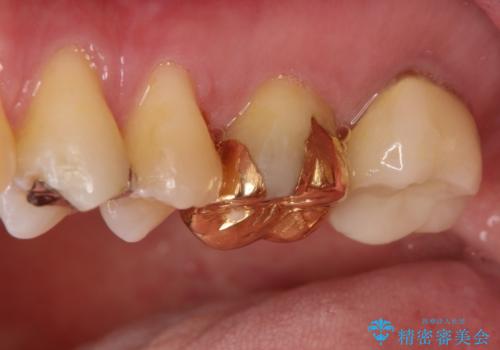

目立つ金歯を自然な色のオールセラミックへ

- 矯正の治療後に目立つ金歯を白くしたいとのことで治療することとなりました。

左上の奥歯に大きな金歯と、その後ろの歯が矯正治療用の仮歯が装着されていました。